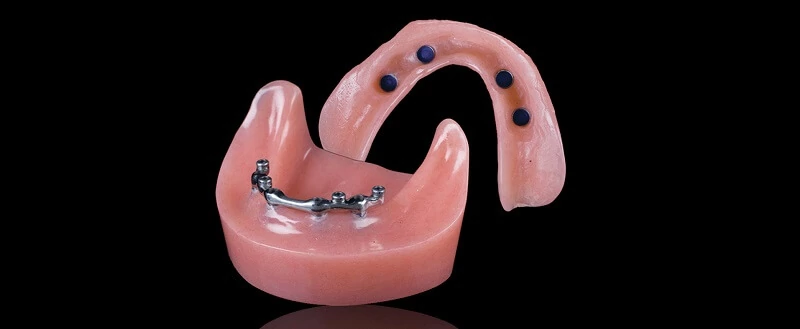

Современные съемные протезы на локаторах: Фото и примеры